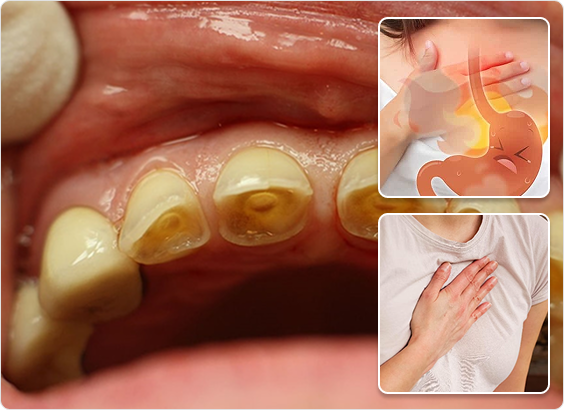

Acidity is a common condition in which the amount of acid increases in the upper part of the stomach. Due to this, people face many health problems like indigestion, vomiting, stomach upset, skin irritation, etc. Apart from this, other symptoms like heartburn, sour burp, flatulence, and nausea also indicate acidity.

Acidity Symptoms

- Heartburn:That burning sensation creeping up your chest is a telltale sign.

- Regurgitation:A bitter taste or even small amounts of food can come back up,leaving you feeling uncomfortable.

- Chronic acidity may cause esophagitis or Barrett"s esophagus.

- It can lead to enamel erosion and dental decay.